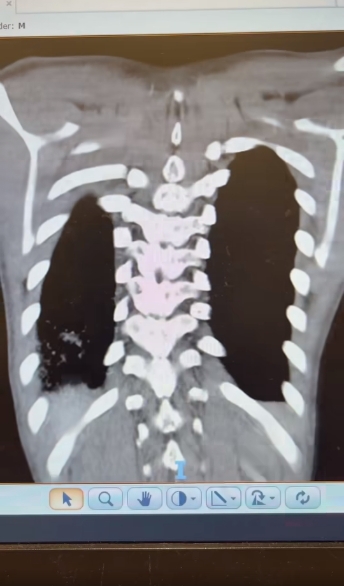

แกลเลอรีรูปภาพ หมอเตือน ตั้งสติก่อนกินตำปูปลาร้า คนไข้อายุ 15 เอกซเรย์ปอดเจอ "โพรงฝีหนอง" 10 ซม.

8 ภาพ หมอเตือน ตั้งสติก่อนกินตำปูปลาร้า คนไข้อายุ 15 เอกซเรย์ปอดเจอ "โพรงฝีหนอง" 10 ซม.

รูปภาพของ หมอเตือน ตั้งสติก่อนกินตำปูปลาร้า คนไข้อายุ 15 เอกซเรย์ปอดเจอ "โพรงฝีหนอง" 10 ซม.

อัลบั้มภาพทั้งหมด หมอเตือน ตั้งสติก่อนกินตำปูปลาร้า คนไข้อายุ 15 เอกซเรย์ปอดเจอ "โพรงฝีหนอง" 10 ซม.